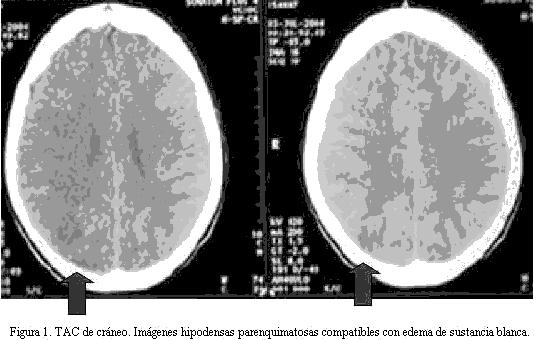

Radiografía de tórax: infiltrado parenquimatoso intersticial y cardiomegalia moderada; ecocardiograma: insuficiencia mitroaórtica leve, con dilatación leve de aurícula izquierda, FEVI 62%. Electroencefalograma: signos de moderada actividad irritativa focal derecha sobre un ritmo de fondo algo más lento para la edad. TAC cráneo: imágenes hipodensas occipitoparietales derechas mal definidas (figura 1).

Las técnicas de neuroimagen son necesarias para el diagnóstico del LEPR. Muestran alteraciones de la señal en la sustancia blanca como consecuencia del edema cerebral que típicamente aparecen en las regiones posteriores y en la unión corticomedular, pudiendo afectar otras zonas de la corteza cerebral, los ganglios basales, el tronco cerebral, el cerebelo e incluso los lóbulos frontales y la sustancia gris (1,6,7).

La RMN es la técnica más sensible para evidenciar dichas lesiones, incluso aquellas pequeñas y focales no demostradas por la TAC. Pero la TAC de cráneo puede mostrar el edema cerebral como imágenes de hipodensidad, por lo que junto a un cuadro clínico compatible, inicialmente no sería necesario realizar otras pruebas de imagen (6).

Nuestro paciente presentó imágenes características en la TAC de cráneo en un contexto clínico sugestivo, apoyando el planteo de LEPR como diagnóstico probable.

La resolución clínico imagenológica evolutiva, con una RMN normal 12 días luego de la TAC inicial, confirmaron el mismo.